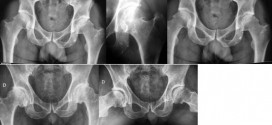

Leer MásCOXITIS

La coxitis. Es una inflamación de la articulación de la cadera provocada generalmente por la tuberculosis. El proceso infeccioso afecta a la membrana sinovial y se extiende posteriormente hacia el cartílago y los ligamentos, con lo que se puede destruir la articulación si no se trata a tiempo. Provoca dolor en el muslo y la rodilla, limitación de los movimientos, …

La coxalgia blenorrágica o artritis gonocócica de la cadera. Es la inflamación de la articulación de la cadera provocada por una infección por gonococos en la articulación de la cadera. La madre naturaleza (Trofología) le proporciona remedios excepcionales para esta patología. Información: Para más información sobre esta enfermedad o patología, si usted cree que es necesario, preguntar a su médico o …

Leer MásCOXALGIA (artritis de la cadera)

La coxalgia o artritis de la cadera. Artritis muy dolorosa causada por una infección de la cadera. Generalmente de origen tuberculoso de la cadera, que afecta principalmente al niño y jóvenes adultos. La cadera es una articulación muy móvil que une el miembro inferior a la pelvis. Además de ser clave en la marcha, pasear, soporta el peso del cuerpo …

La condromatoris. Formación de múltiples condromas en las epífisis de los huesos (encondroma), especialmente en las falanges. Suelen ser simétricos, ocasionan acortamiento óseo y es posible su transformación en condrosarcoma. Las manifestaciones clínicas son abultamientos nudosos de los dedos o la discrepancia longitud de los miembros. Los niños afectos empiezan a claudicar al segundo año de vida así como a …

La condrocalcinosis. Enfermedad en la que se caracterizada por el depósito de calcio en las articulaciones periféricas de cartílagos articulares, en los meniscos y en los ligamentos. Puede incluir crisis intermitentes de artritis aguda, similares a los de la gota, o de persistir de forma crónica. Se parece a la gota y aparece sobre todo a las personas mayores de …